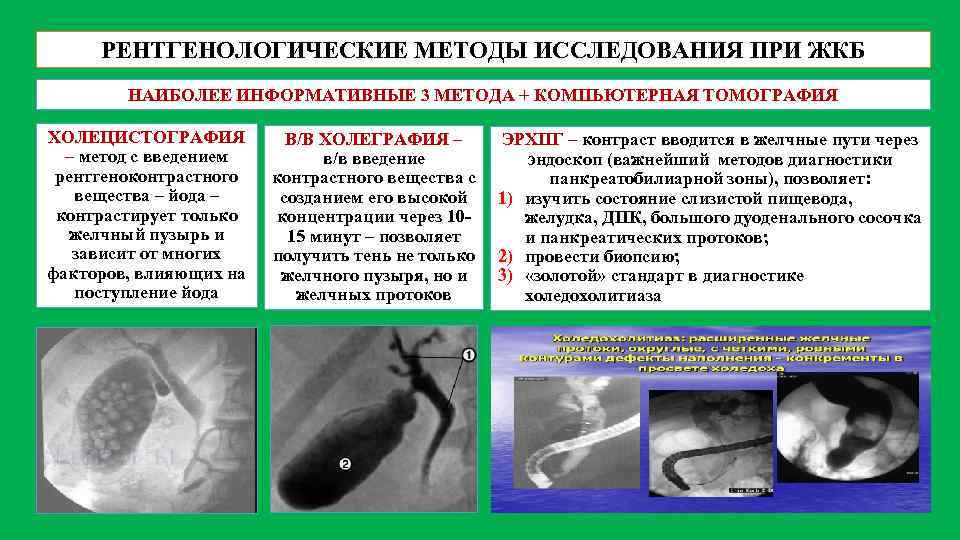

Цирроз печени на мрт с контрастом. Цирроз печени снимки мрт. Цирроз печени снимки кт. Метод диагностики желчекаменной болезни. Методы рентгенологического исследования при желчнокаменной болезни. Рентгенологические методы исследования желчного пузыря. Методы исследования больных с заболеваниями желчного пузыря.

Метод диагностики желчекаменной болезни. Методы рентгенологического исследования при желчнокаменной болезни. Рентгенологические методы исследования желчного пузыря. Методы исследования больных с заболеваниями желчного пузыря. Онкология головного мозга. Раковые заболевания головного мозга.

Проявления поражения теменной доли.. Объемное образование головного мозга. ЭРХПГ при холедохолитиазе заключение. Желчнокаменная болезнь лучевая диагностика. Эндоскопическое исследования механической желтухи. Лучевые исследования при желтухе.

ЭРХПГ при холедохолитиазе заключение. Желчнокаменная болезнь лучевая диагностика. Эндоскопическое исследования механической желтухи. Лучевые исследования при желтухе. Позитронно-эмиссионная томография мозга. ПЭТ кт головного мозга. ПЭТ кт опухоли головного мозга. Позитронно-эмиссионная томография опухоли.